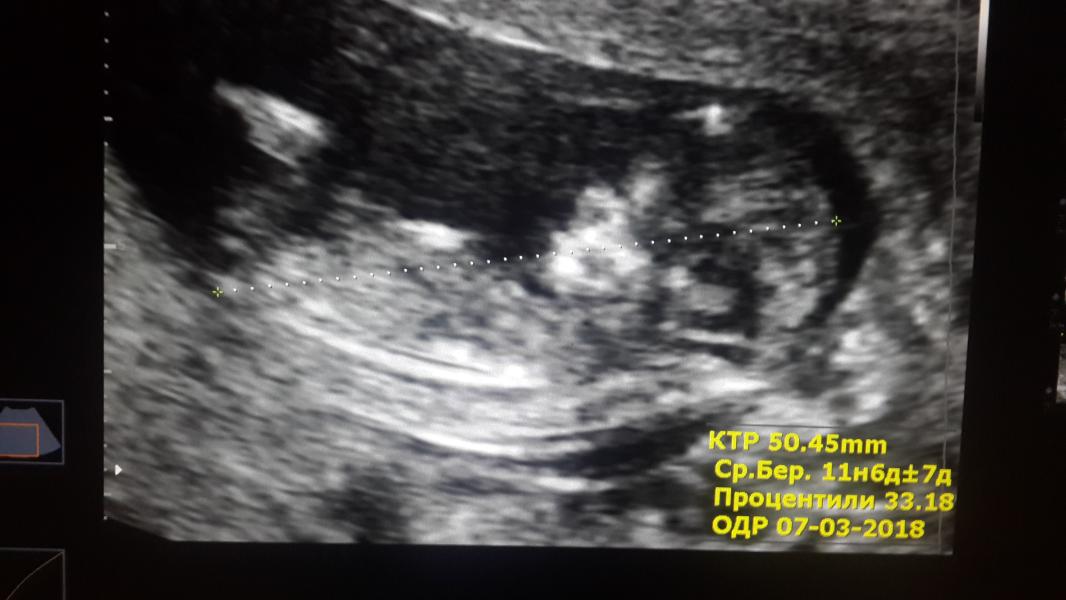

Привет всем👋 А мы сегодня были на 1 скрининге!! Первая встреча с нашим крохой)))💞💞💞